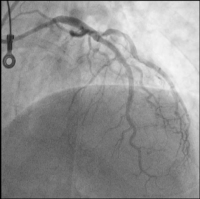

LAD

Abbildung 2: LAD: im mittleren Gefäßabschnitt langstreckig verkalkt, wirksam stenosiert

LAD: Ballon

Abbildung 7: LAD: NEON™ NC 2,75/20 mm Ballon (Cordis): Dissektion